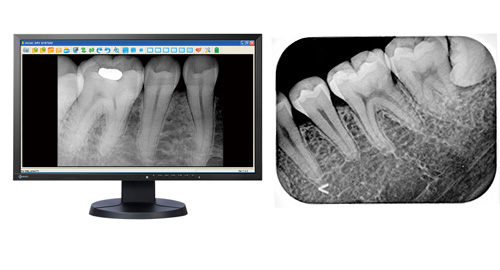

レントゲンとは

レントゲンにはお口全体を撮影するパノラマレントゲンと2~3本の歯を撮影するデジタルレントゲンがあります。

それに対して、小さいサイズのデンタルレントゲンは細かな虫歯や根の先の状態などパノラマレントゲンよりも詳しい情報を得ることができます。